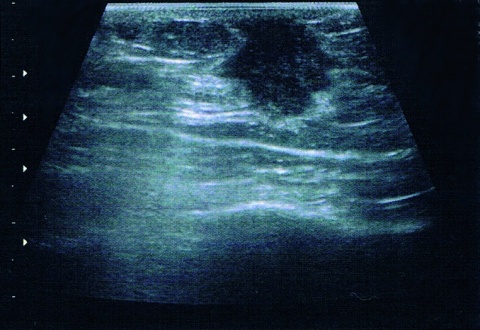

Fallbeispiel: Seminomatöser Hodentumor mit kontralateraler testikulärer intraepithelialer Neoplasie als Zufallsbefund In unserer urologischen Ambulanz (Bundeswehrkrankenhaus Ulm) stellte sich ein 28-jähriger Patient zur Abklärung einer Mikrohämaturie…